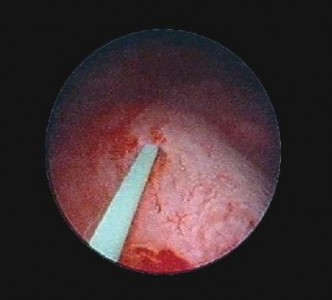

Hình 2.8. Đặt dây dẫn đường vào niệu quản

(Nguồn: chụp tại Bệnh Viện Trường Đại Học Y - Dược Huế)